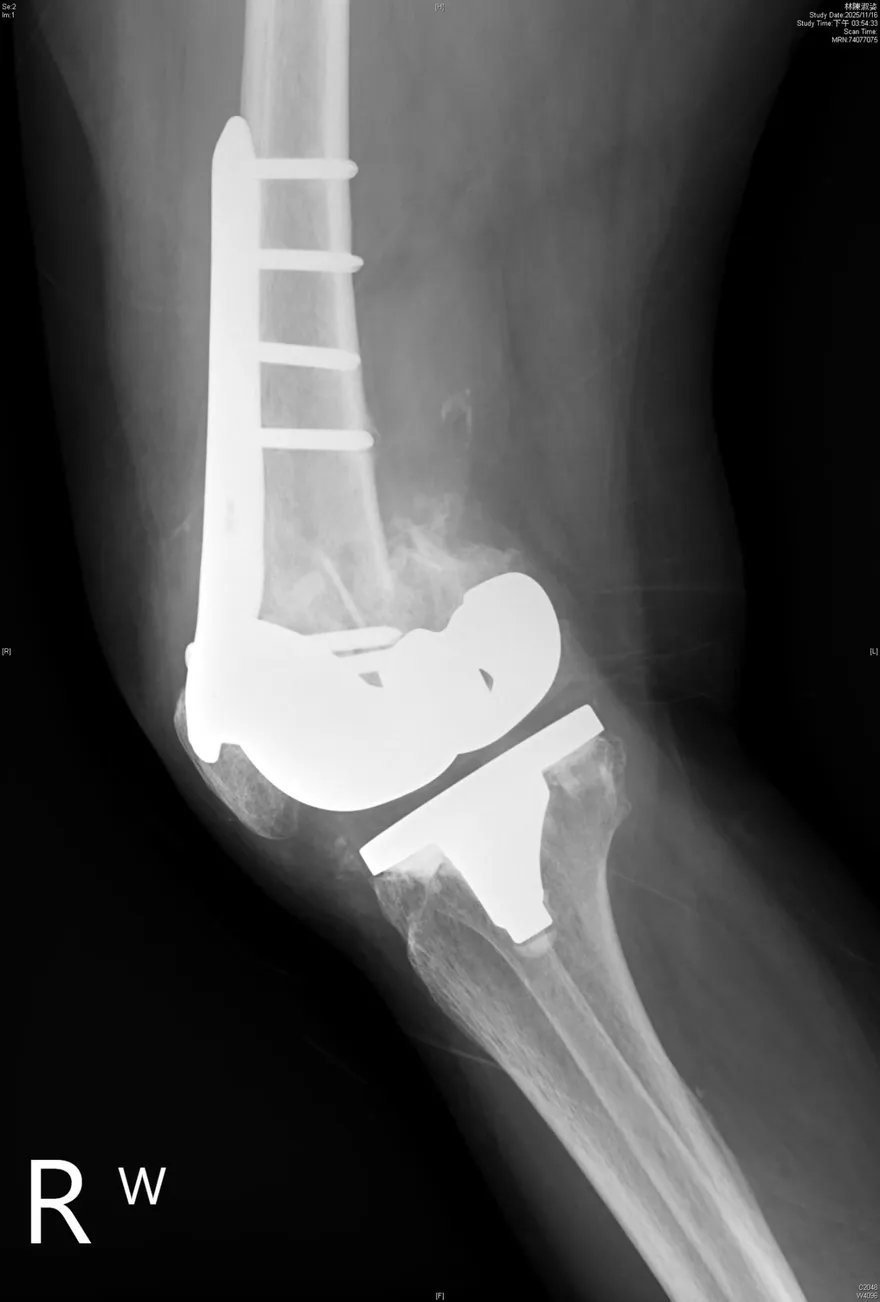

跌一跤膝蓋「啪」一聲!8旬嬤換人工膝關節還是骨折2次

全人工膝關節置換

骨質疏鬆

骨折

退化性膝關節炎

膝關節手術

高齡骨折風險